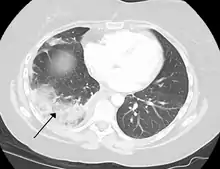

Chest CT (axial lung window)